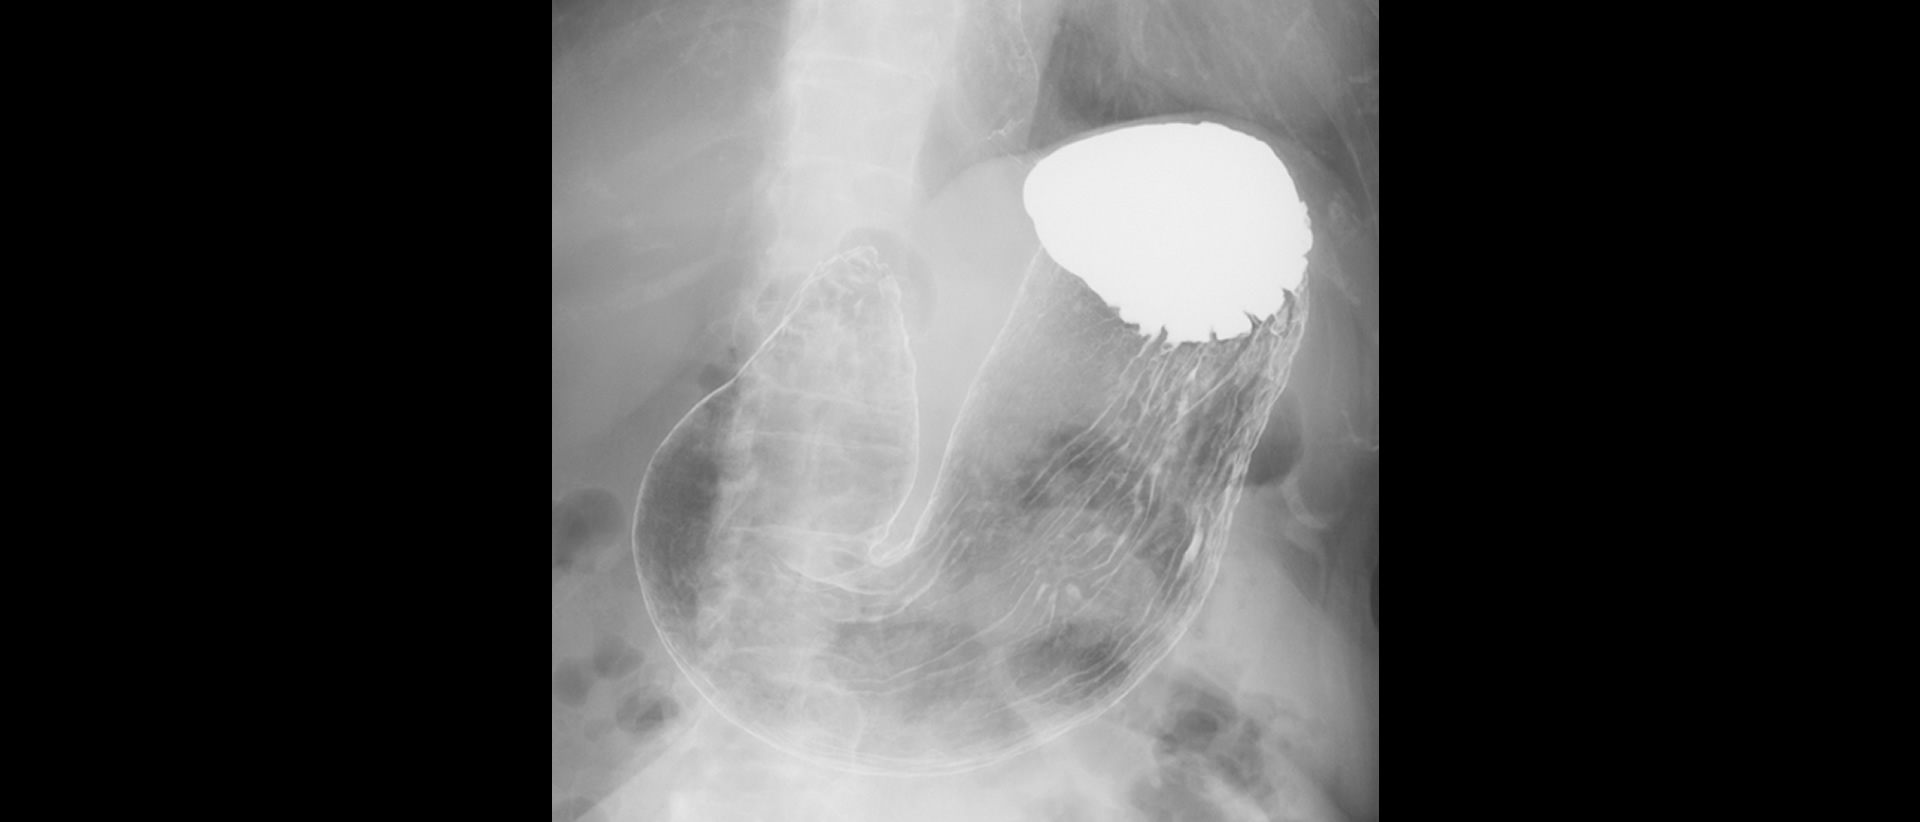

Médico Radiologo

Artículos orientados a Médicos Radiólogos con casos reales de nuestras clínicas

Leer artículos